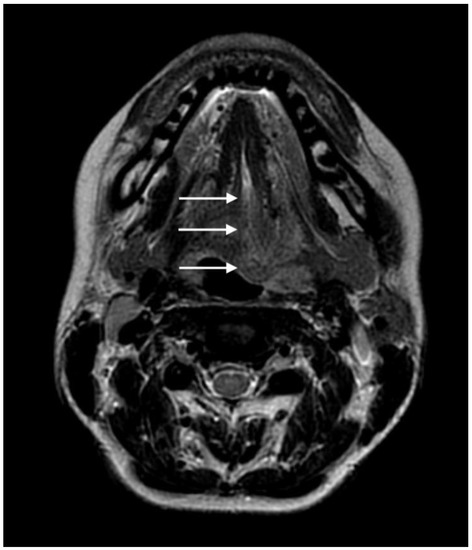

2.2. Diagnosis